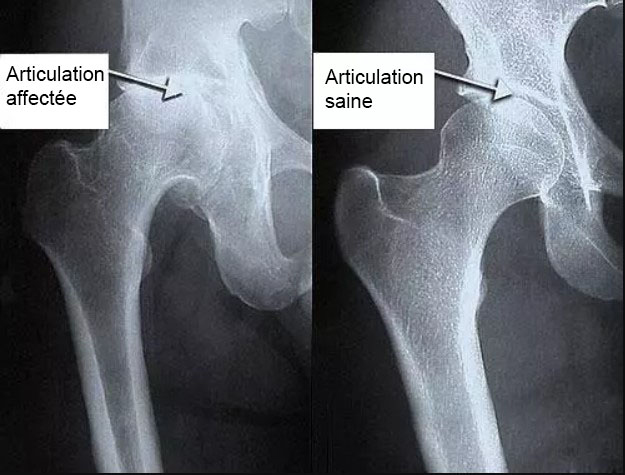

Traitement de l'articulation de la hanche d'un patient âgé de 44 ans. La douleur atroce qui a torturé le patient pendant 2 ans, a été complètement guérie :